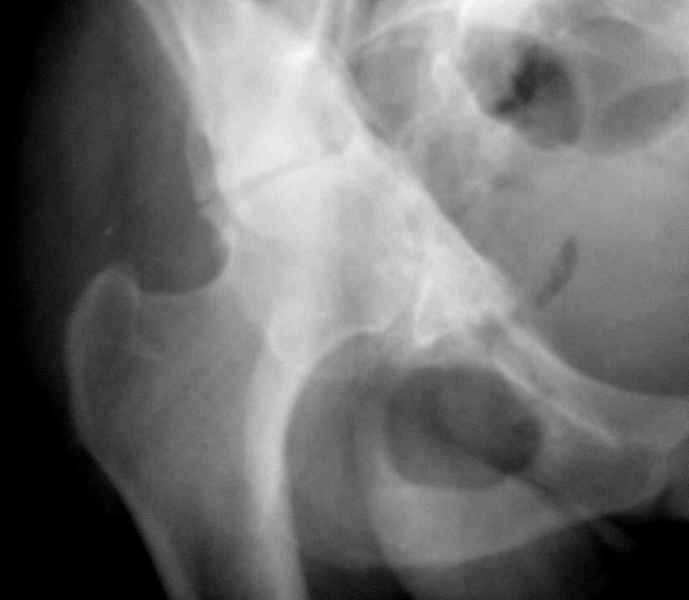

Может быть целесообразнее выполнить синтез передней колонны винтом, заднюю укрепить пластиной из заднего доступа, а затем установить вертлужный компонент press fit, либо по типу Jumbo cup, с пластикой дна в одну сессию.

при более внимательном анализе КТ, передняя колонна выглядит сросшейся, остается синтезировать заднюю?Похоже был низкий двухколонный перелом или перелом передней с задним полупоперечником?